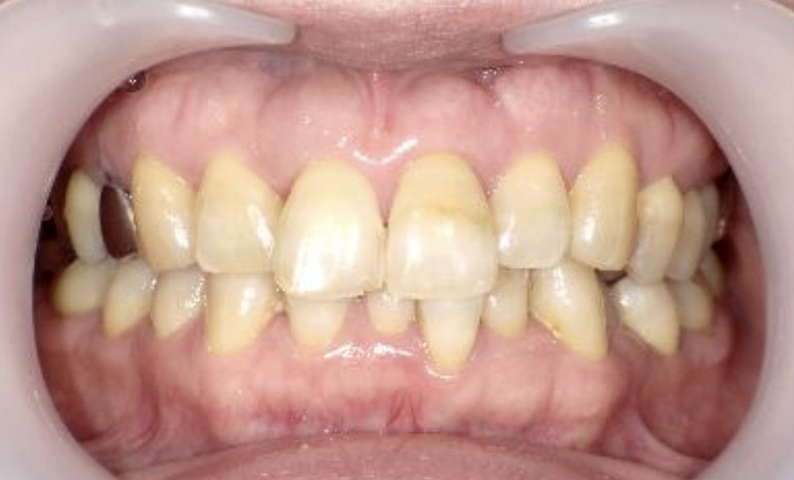

症例_022 上下顎の部分矯正

治療期間:9ヶ月金額:51万円+税女性前歯のガタガタ八重歯

| Before | After |